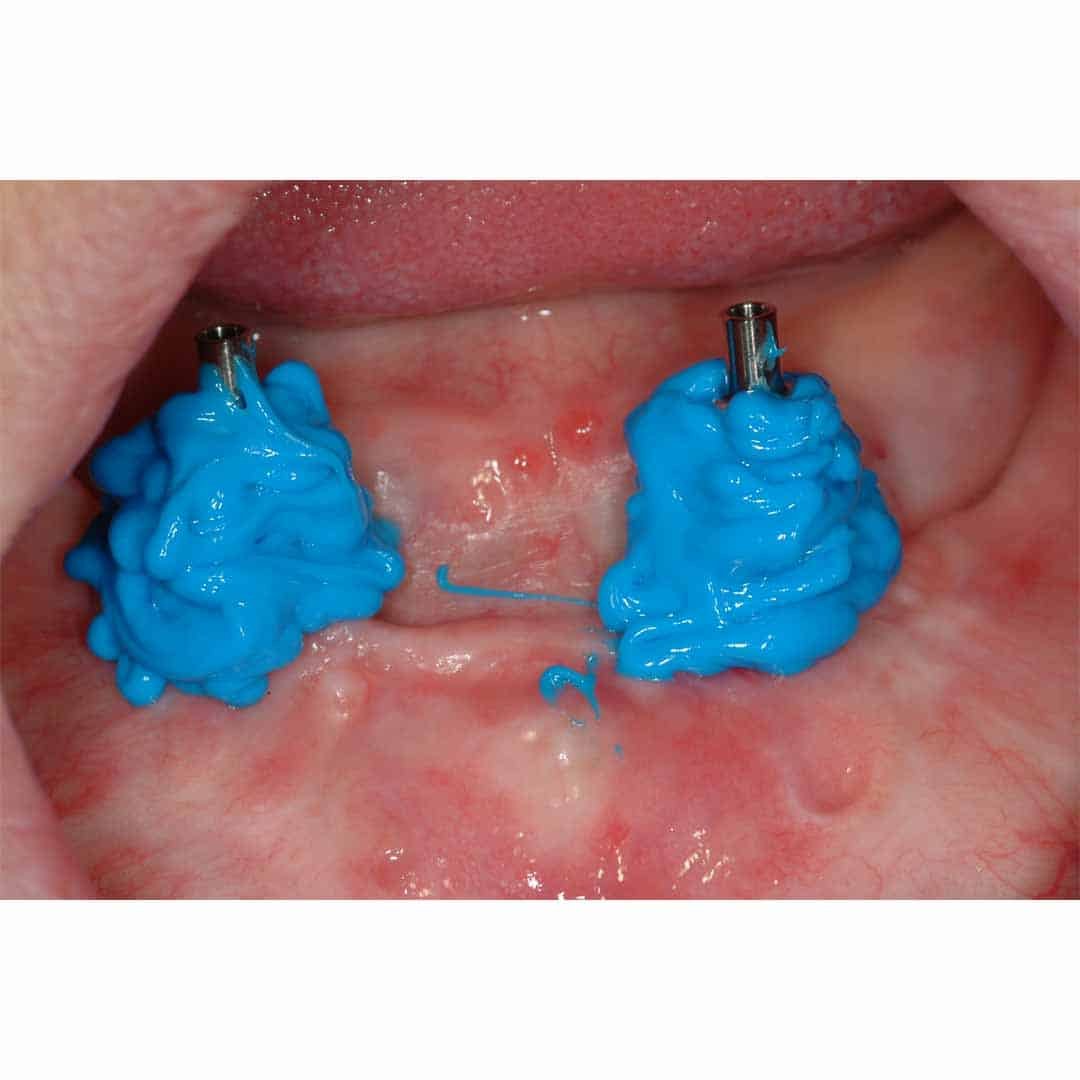

✓ Zeer geschikt als implantaat afdrukmateriaal (shore A-60)

Panasil® monophase Medium is leverbaar als 380 ml jumbo cartridge en in het geoptimaliseerde 50 ml cartridge systeem. Panasil® monophase Medium is tevens zeer geschikt als afdrukmateriaal voor de edentate patiënt.